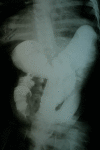

Schimke immuno-osseous dysplasia is a rare autosomal recessive multisystem disorder characterized by steroid-resistant nephrotic syndrome, immunodeficiency, and spondyloepiphyseal dysplasia. Mutations in SWI/SNF2 related, matrix associated, actin dependent regulator of chromatin, subfamily a-like 1 (SMARCAL1) gene are responsible for the disease. The present report describes, for the first time, a Schimke immuno-osseous dysplasia child with SMARCAL1 missense mutation (R561H) and manifestations of intussusception secondary to Epstein-Barr virus-negative non-Hodgkin lymphoma, who expired due to septicemia following chemotherapy. The report emphasizes the necessity of more limited immunosuppressive protocols in Schimke immuno-osseous dysplasia patients with lymphoproliferative disorders.